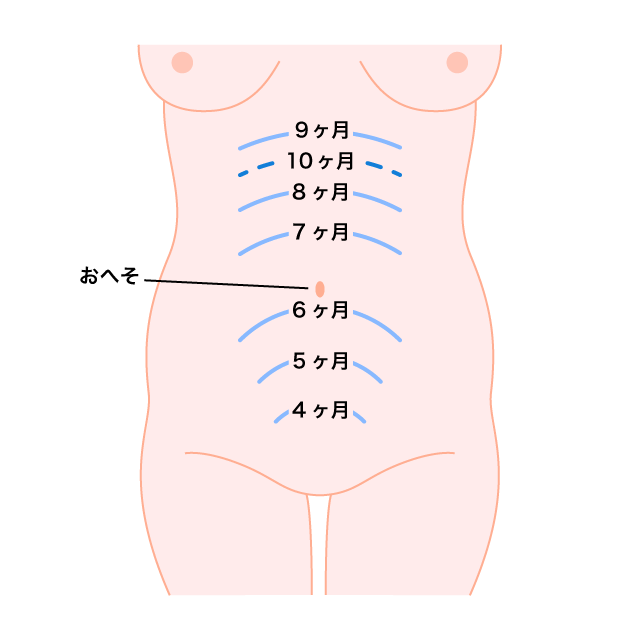

妊娠中のおなかの膨らみ方は?いつから変化する?どこから?-おむつのムーニー 公式 ユニ・チャーム。

妊娠から出産までに母胎に起こる変化 妊娠中期ホームメイト。